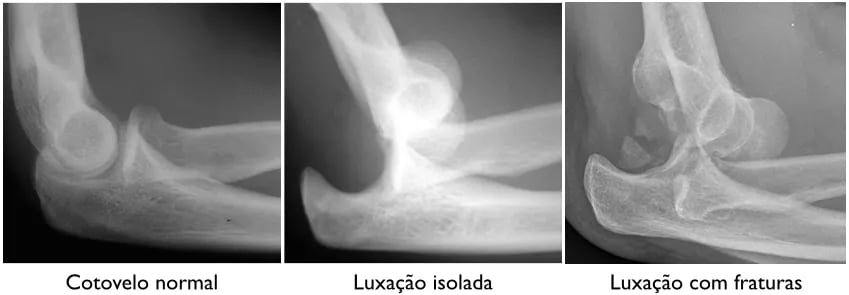

Luxação do Cotovelo

A luxação do cotovelo é a perda de congruência entre o braço e o antebraço. O cotovelo é uma articulação bastante estável, tanto pela sua anatomia óssea como ligamentar. Geralmente é preciso um trauma grave ou fraturas associadas para ocorrer a luxação.